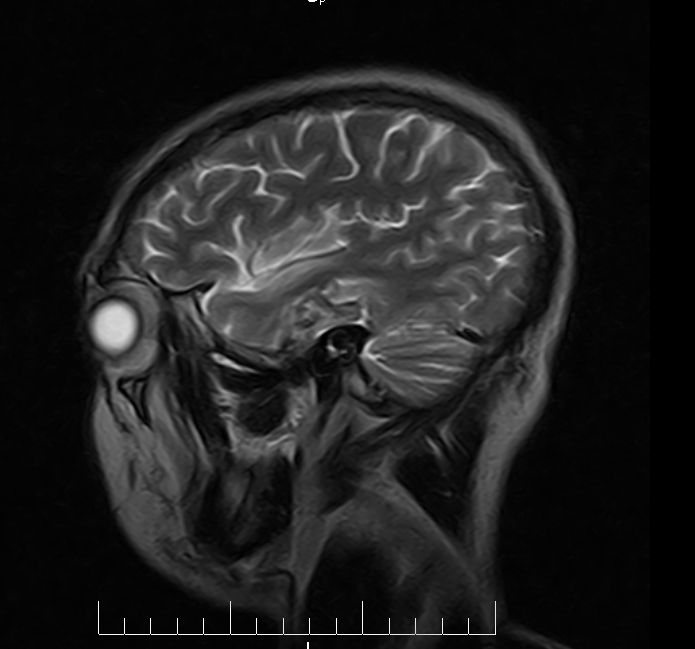

标题: MRI2379:30岁,男,癫痫10年,请各位看一下;CT示:左颞叶钙 [打印本页]

左颞叶区见不规则点状混杂信号影

考虑血管畸形

支持2楼 左颞叶区见不规则点状混杂信号影,考虑动静脉畸形。

考虑左侧颞叶脑血管畸形(avm)。

考虑左侧颞叶脑血管畸形(avm)。----t1低等高混杂信号,t2等高信号周边较多流空血管影[冠状位明显],mra左侧大脑中动脉受压,远侧聚集.

海绵状血管瘤

支持海绵状血管瘤!

考虑avm,建议行增强扫描,看供血a与引流v,以明确诊断。